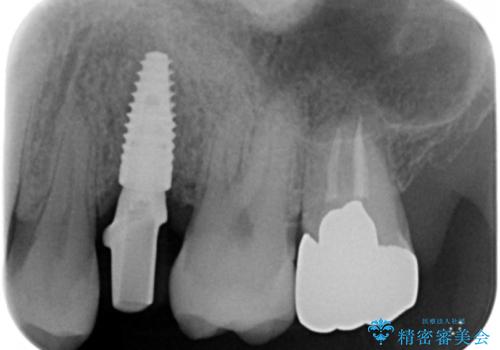

残根状態になっている左上の小臼歯(左上5)を精査したところ、う蝕が歯肉縁下まで進行しており保存不可能な状態でした。

患者様のご希望により、抜歯後インプラント治療を行いました。

骨の厚みが不足していたため、インプラントの埋入と同時にソケットリフト(上顎骨に骨を増やす手術)を行いました。

インプラントの種類:ストローマン BLT